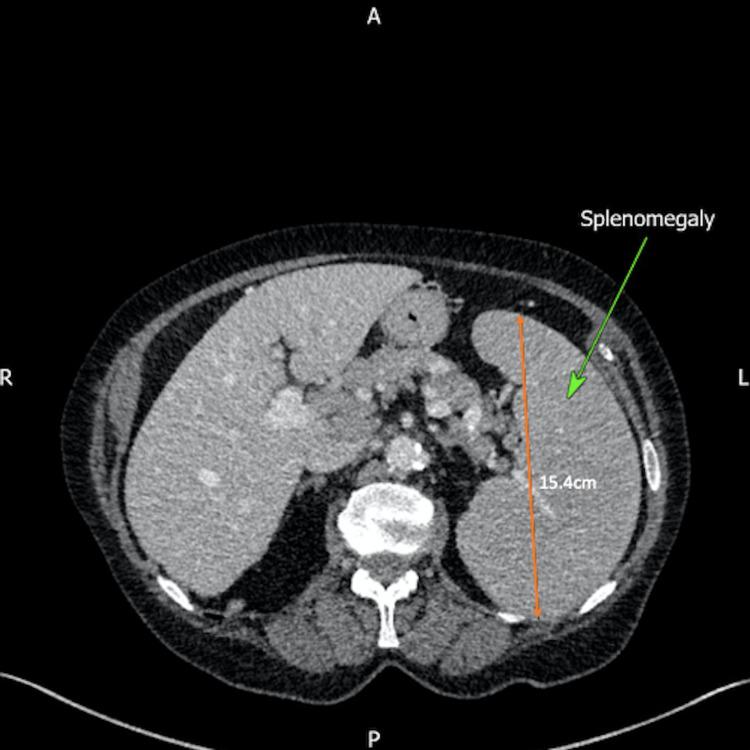

Chronic lymphocytic leukaemia (CLL) is a malignant monoclonal expansion of B lymphocytes, with accumulation of abnormal lymphocytes in the blood, bone marrow, spleen, lymph nodes and liver. It is mainly a disease of the elderly population. Though extra-nodal involvement is common, cervical and vulvovaginal involvement by CLL is particularly uncommon. In this case report, we discuss the case of cervical involvement of CLL in an 84-year-old patient who presented to rapid-access gynaecological clinic following concerns of persistent postmenopausal bleeding. Previously the patient was known to haematology with a well-controlled diagnosis of CLL since 2007. The initial examination was significant for an enlarged, irregular cervix, whereby a punch biopsy was then obtained. Histological analysis revealed evidence of CLL within the cervix.

慢性淋巴细胞白血病(CLL)是B淋巴细胞的恶性单克隆增殖,异常淋巴细胞在血液、骨髓、脾脏、淋巴结和肝脏中积聚。它主要是一种老年人群的疾病。虽然结外受累很常见,但CLL累及宫颈和外阴阴道尤其罕见。在本病例报告中,我们讨论了一名84岁患者CLL累及宫颈的病例,该患者因绝经后持续出血而就诊于快速通道妇科门诊。该患者自2007年以来一直患有CLL,此前血液科已对其进行了病情控制良好的诊断。初步检查发现宫颈肿大且形态不规则,随后进行了组织活检。组织学分析显示宫颈内存在CLL的证据。